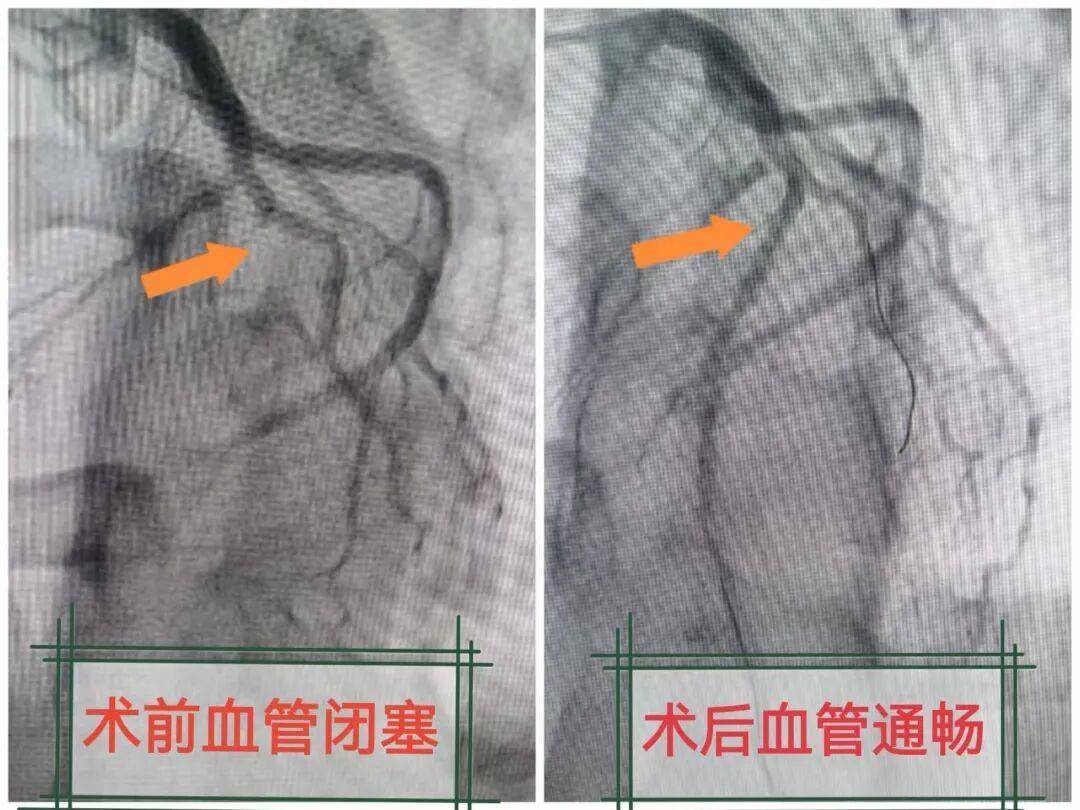

完善冠脉造影检查后,发现了孙先生心梗的元凶:心脏最重要的“生命线”——前降支中段完全闭塞。这条血管负责为心脏大面积心肌供血,一旦堵塞,心肌将迅速缺血坏死,心源性猝死随时可能发生。

医疗团队争分夺秒,心血管内科四病区主任、主任医师何文华凭借熟练的操作技巧,顺利通过导管向闭塞血管内精准溶栓,并成功植入一枚支架。当血流重新通畅的那一刻,监护仪上的心率逐渐平稳,这位年轻的生命,被从死亡的悬崖边硬生生拉了回来。目前,孙先生生命体征平稳,正在进一步康复治疗中。